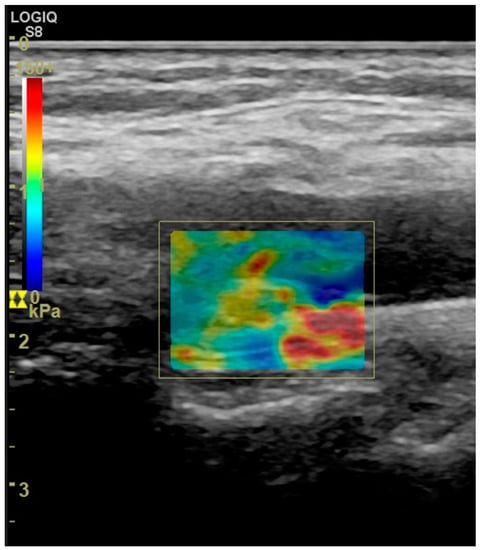

5. Elastography of Carotid Atherosclerotic Disease

- Bamber, J.; Cosgrove, D.; Dietrich, C.F.; Fromageau, J.; Bojunga, J.; Calliada, F.; Cantisani, V.; Correas, J.M.; D’Onofrio, M.; Drakonaki, E.E.; et al. EFSUMB guidelines and recommendations on the clinical use of ultrasound elastography. Part 1: Basic principles and technology. Ultraschall Med. 2013, 34, 169–184. [Google Scholar] [CrossRef]

- Di Leo, N.; Venturini, L.; de Soccio, V.; Forte, V.; Lucchetti, P.; Cerone, G.; Alagna, G.; Caratozzolo, M.; Messineo, D.; Di Gioia, C.; et al. Multiparametric ultrasound evaluation with CEUS and shear wave elastography for carotid plaque risk stratification. J. Ultrasound 2018, 21, 293–300. [Google Scholar] [CrossRef]

- Liu, F.; Yong, Q.; Zhang, Q.; Liu, P.; Yang, Y. Real-Time Tissue Elastography for the Detection of Vulnerable Carotid Plaques in Patients Undergoing Endarterectomy: A Pilot Study. Ultrasound Med. Biol. 2015, 41, 705–712. [Google Scholar] [CrossRef]

- Lou, Z.; Yang, J.; Tang, L.; Jin, Y.; Zhang, J.; Liu, C.; Li, Q. Shear Wave Elastography Imaging for the Features of Symptomatic Carotid Plaques: A Feasibility Study. J. Ultrasound Med. 2017, 36, 1213–1223. [Google Scholar] [CrossRef]

- Ramnarine, K.V.; Garrard, J.W.; Kanber, B.; Nduwayo, S.; Hartshorne, T.C.; Robinson, T.G. Shear wave elastography imaging of carotid plaques: Feasible, reproducible and of clinical potential. Cardiovasc. Ultrasound 2014, 12, 49. [Google Scholar] [CrossRef]

- Garrard, J.W.; Ummur, P.; Nduwayo, S.; Kanber, B.; Hartshorne, T.C.; West, K.P.; Moore, D.; Robinson, T.G.; Ramnarine, K.V. Shear Wave Elastography May Be Superior to Greyscale Median for the Identification of Carotid Plaque Vulnerability: A Comparison with Histology. Ultraschall Med. 2015, 36, 386–390. [Google Scholar] [CrossRef]